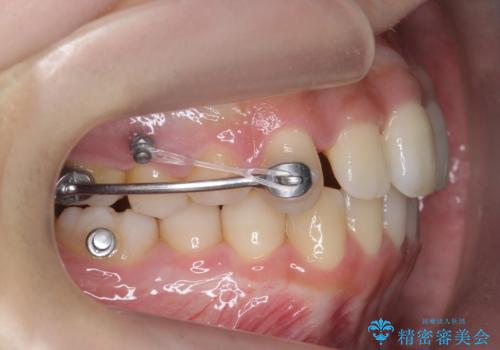

後ろに下げるために、ワイヤー矯正の前にカリエールという装置を使用しました。

- 矯正装置

- ワイヤー矯正

- 2年11ヶ月